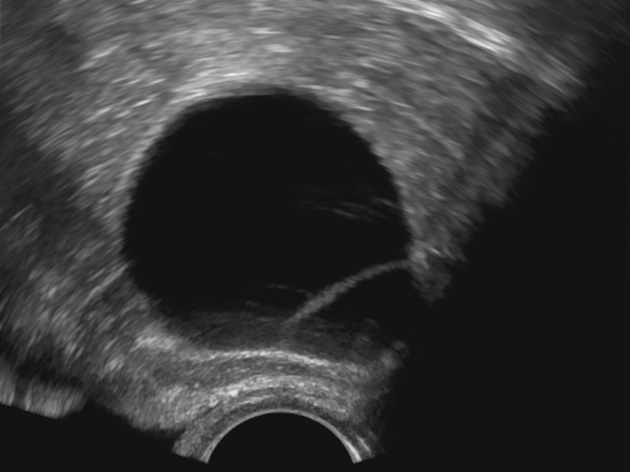

К «практически наверняка доброкачественным» относятся образования, имеющие «классическую» эхографическую картину доброкачественного образования (простая и однокамерная киста, геморрагическая киста, эндометриома, дермоидная киста и фиброма) (рис. 1–6). Понятие однокамерной кисты относительно новое и подразумевает наличие в полости кисты ≥1 неполной перегородки, локальных утолщений на стенке высотой до 3 мм, внутренних эхо в полости (рис. 2). Одиночная тонкая (≤3 мм) перегородка в полости кисты считается доброкачественной находкой [22].

Рис. 3. Геморрагическая киста яичника. Киста с сетчатым рисунком и сгустком в виде эхогенного компонента с ангулярными контурами в полости

Fig. 3. Hemorrhagic ovarian cyst: a cyst with a mesh pattern and a blood clot presenting in the form of an echogenic component with angular contours in the cavity